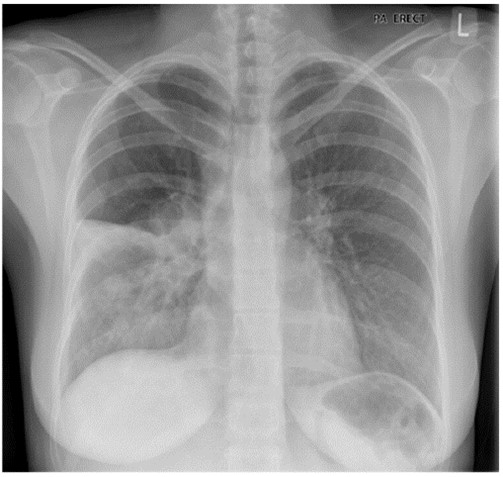

Bệnh phổi tắc nghẽn mãn tính (BPTNMT) là một bệnh hô hấp phổ biến có thể phòng và điều trị được. Đây là bệnh lý không đồng nhất, đặc trưng bởi các triệu chứng hô hấp mạn tính (khó thở, ho, khạc đàm) và các đợt cấp do tình trạng bất thường của đường thở và hoặc phế nang gây ra tắc nghẽn đường thở dai dẳng và thường tiến triển nặng dần.